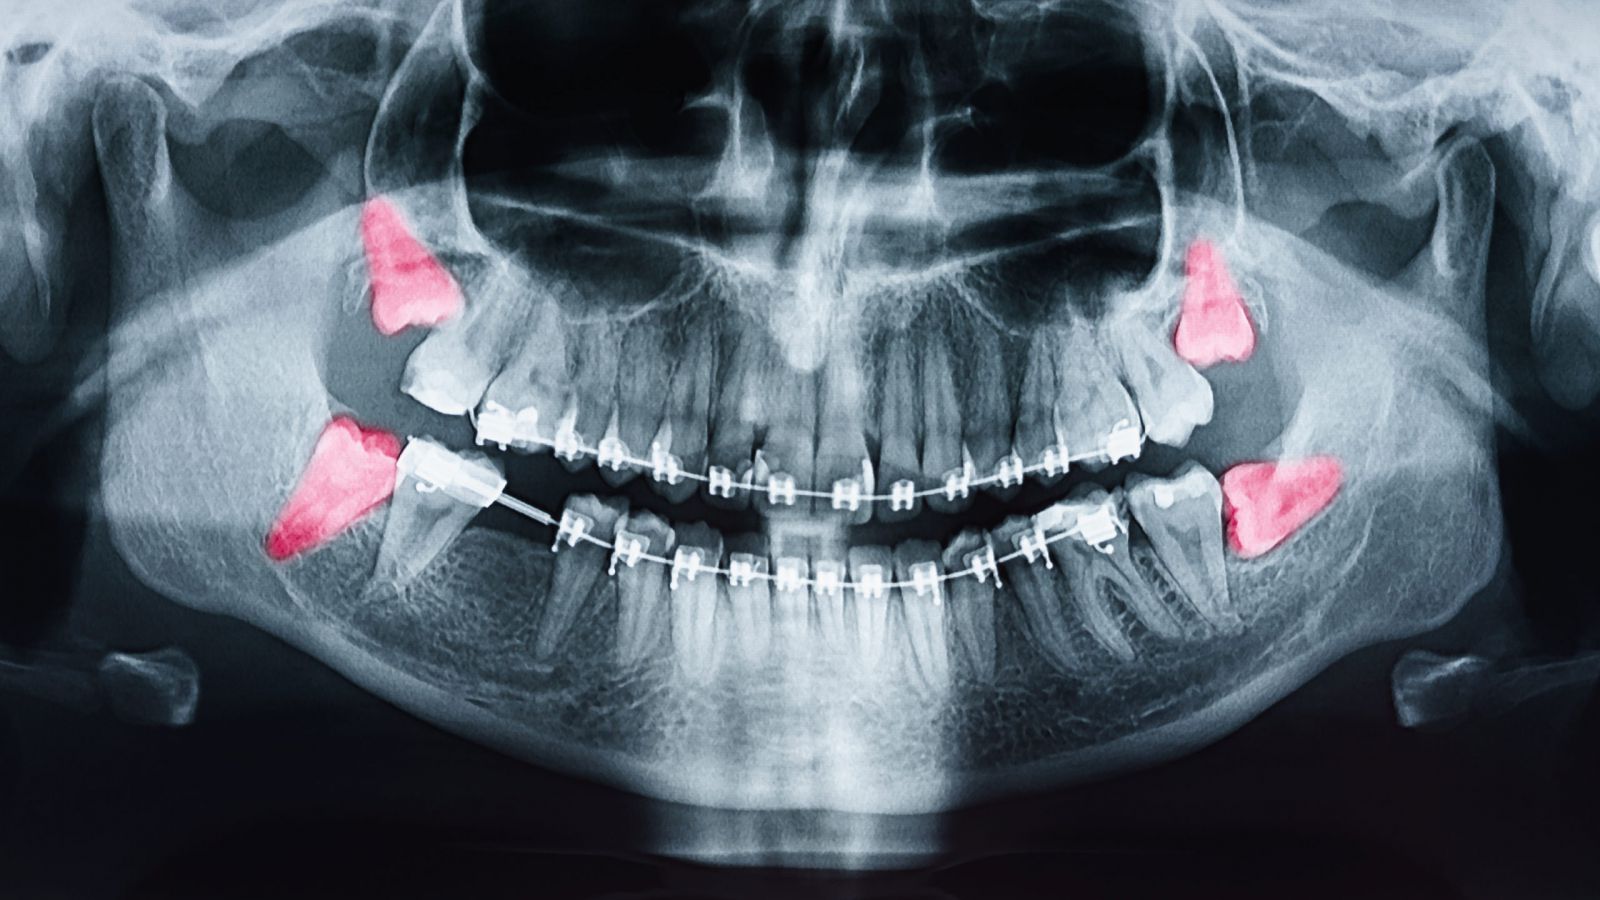

• Phẫu thuật trong miệng là tiểu phẫu cần tiến hành trong các can thiệp nha khoa với các chỉ định: Nhổ răng trong nắn chỉnh răng, nhổ răng ngầm, nhổ răng thừa, nhổ răng kẹ, lạc chỗ, tháo vít nẹp xương, cấy implant, tạo hình viền lợi, cắt phanh môi, bắt và tháo vít neo chặn, thay các phụ kiện trong quá trình làm răng implant,...và các can thiệp có dùng thuốc gây tê, có chảy máu khác trong miệng

Phẫu thuật trong miệng là tiểu phẫu cần tiến hành trong các can thiệp nha khoa với các chỉ định: Nhổ răng trong nắn chỉnh răng, nhổ răng ngầm, nhổ răng thừa, nhổ răng kẹ, lạc chỗ, tháo vít nẹp xương, cấy implant, tạo hình viền lợi, cắt phanh môi, bắt và tháo vít neo chặn, thay các phụ kiện trong quá